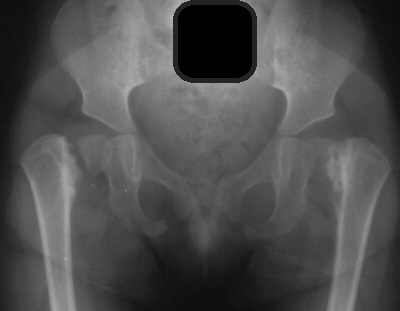

RADIOGRAPHIC FINDINGS:

- femoral-neck shaft angle below 90 degrees

- more vertical position of the epiphyseal plate with Hilgenreiner's-epiphyseal

angle greater than 40 degrees (normal is less than 25 degrees)

- triangular metaphyseal fragment in inferior femoral neck surrounded

by inverted Y (sine qua non)